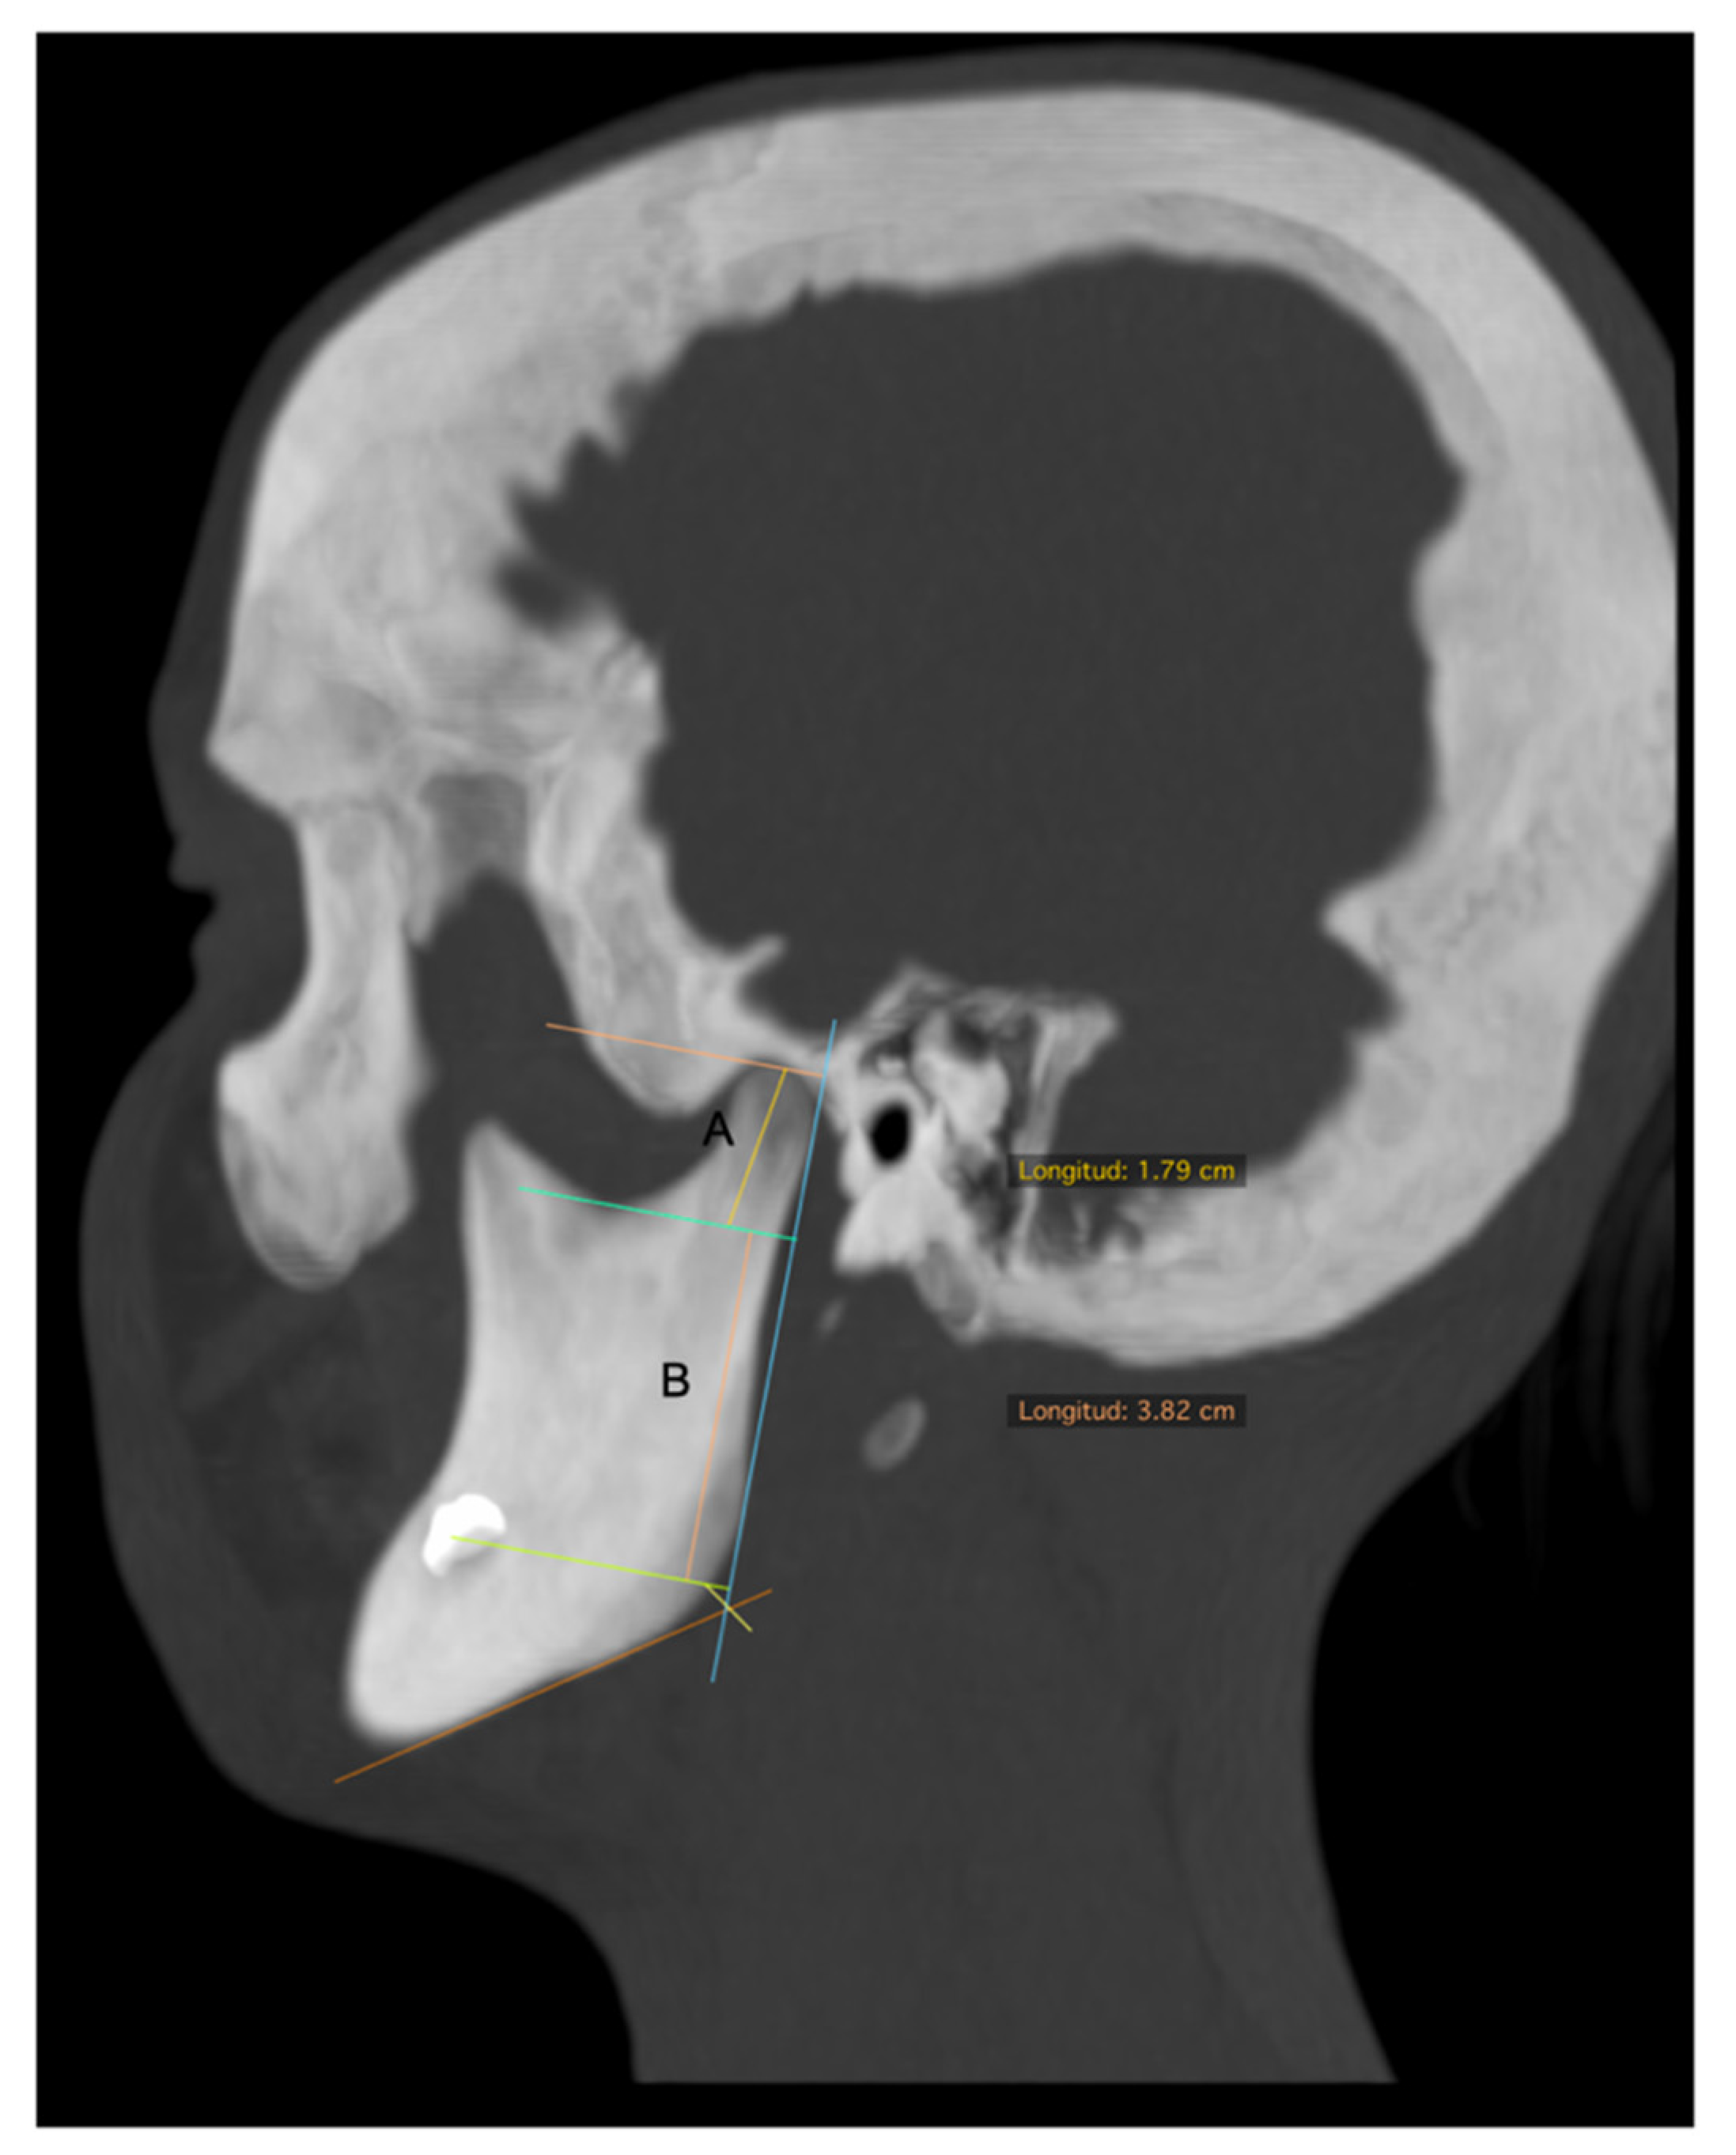

| Condylar length | In the sagittal view, a line parallel to a tangent to the posterior ridge of the mandibular ramus was traced and extended from the most superior point of the condyle to a perpendicular line, passing through the most inferior point of the mandibular notch. This length was obtained in a corrected image of the axial axis of the mandibular ramus (Figure 2A). |

| Mandibular ramus length | In the sagittal view of 3D reconstruction, a line perpendicular to the Frankfort plane, was traced and extended from the deepest point of the notch to the inferior ridge of mandibular body (Figure 2B). |